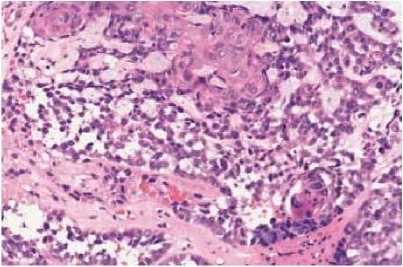

Gambar 1.Karsinoma sel skuamosa

berkeratin5

terdiferensiasi,tersusun atas sekumpulan sel yang berbentuk sarang-sarang padat (tipe Regaud).5

berkeratin. 5

Tipe non-terdiferensiasi memiliki dua pola histologi berbeda. Tipe Regaud merupakan sekumpulan sel epiteoild berbatas tegas dengan jaringan ikat fibrosa dan sel limfosit yang mengitari. Berbeda dengan tipe Schminke yang memiliki sel epithelial neoplastik yang difus, dan diselingi dengan sel radang.4,5

terdiferensiasi terdiri atas sejumlah sel yang tumbuh membentuk gambaran syncytial yang tersusun difus (tipe Schmincke).5